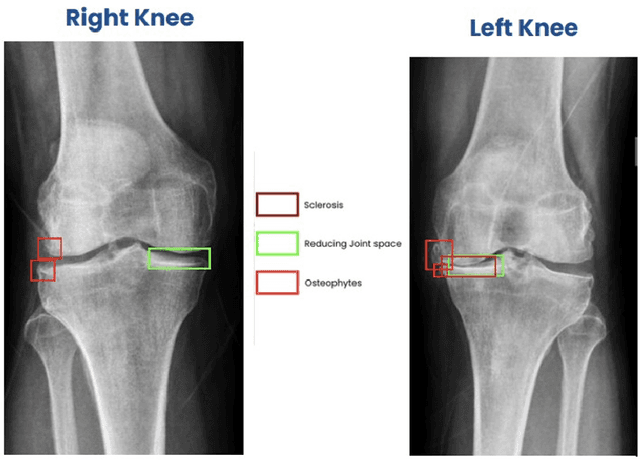

Abstract:Introduction: Bone health disorders like osteoarthritis and osteoporosis pose major global health challenges, often leading to delayed diagnoses due to limited diagnostic tools. This study presents an AI-powered system that analyzes knee X-rays to detect key pathologies, including joint space narrowing, sclerosis, osteophytes, tibial spikes, alignment issues, and soft tissue anomalies. It also grades osteoarthritis severity, enabling timely, personalized treatment. Study Design: The research used 1.3 million knee X-rays from a multi-site Indian clinical trial across government, private, and SME hospitals. The dataset ensured diversity in demographics, imaging equipment, and clinical settings. Rigorous annotation and preprocessing yielded high-quality training datasets for pathology-specific models like ResNet15 for joint space narrowing and DenseNet for osteoarthritis grading. Performance: The AI system achieved strong diagnostic accuracy across diverse imaging environments. Pathology-specific models excelled in precision, recall, and NPV, validated using Mean Squared Error (MSE), Intersection over Union (IoU), and Dice coefficient. Subgroup analyses across age, gender, and manufacturer variations confirmed generalizability for real-world applications. Conclusion: This scalable, cost-effective solution for bone health diagnostics demonstrated robust performance in a multi-site trial. It holds promise for widespread adoption, especially in resource-limited healthcare settings, transforming bone health management and enabling proactive patient care.